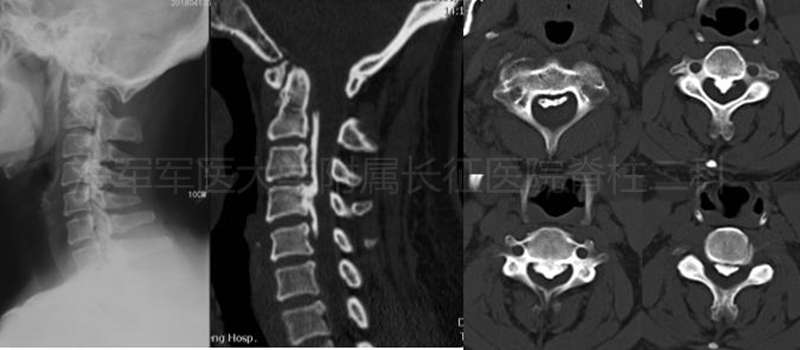

术前侧位平片和矢状位、水平位CT

术前矢状位、水平位MRI

术后侧位平片矢状位MRI和矢状位、水平位CT

术前CT及平片

术前MRI

术后平片

术后CT

术后MRI